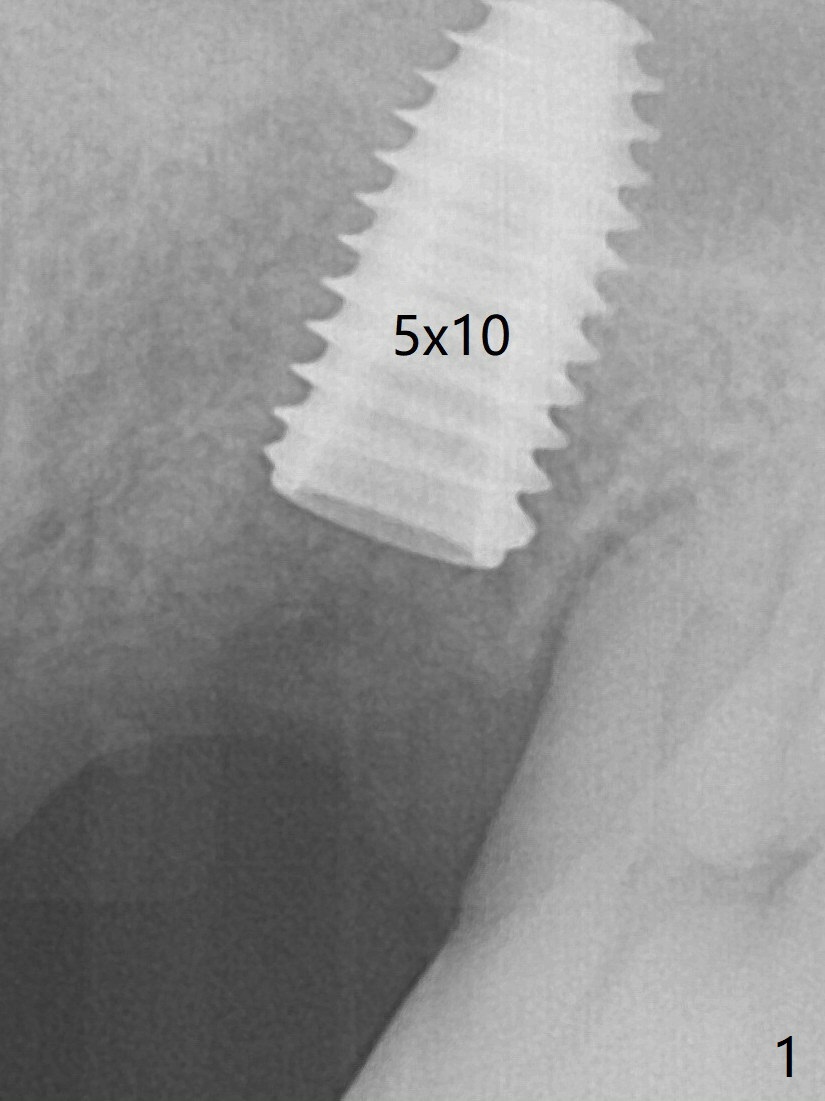

Six months post 2nd placement at #14, the 5x11 mm IBS implant is unstable. The patient smokes a cigarette a day.  After implant removal, the palatal wall of the osteotomy is intact, although low.  With removal of minimal granulation tissue, a 5x10 mm IS dummy implant is placed with stability and slightly subgingival palatal (Fig.1,2).  The abutment and implant are stable 4.5 months postop (Fig.5); a provisional is fabricated for progressive loading.